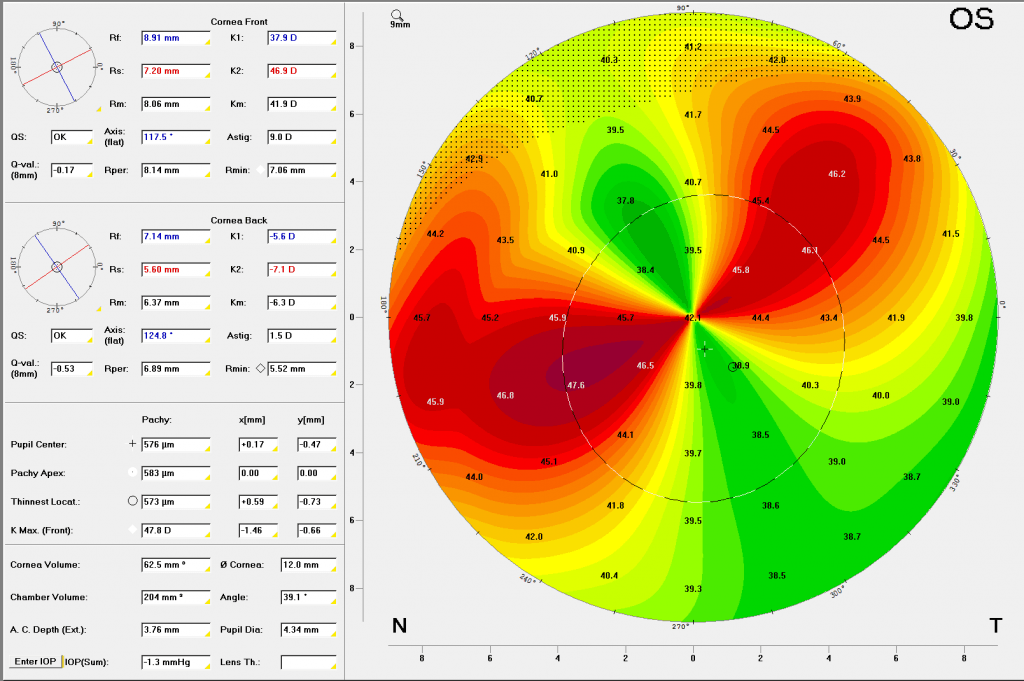

This corneal topography map shows that the patient’s TMD has resulted in significant corneal asymmetry and therefore astigmatism.